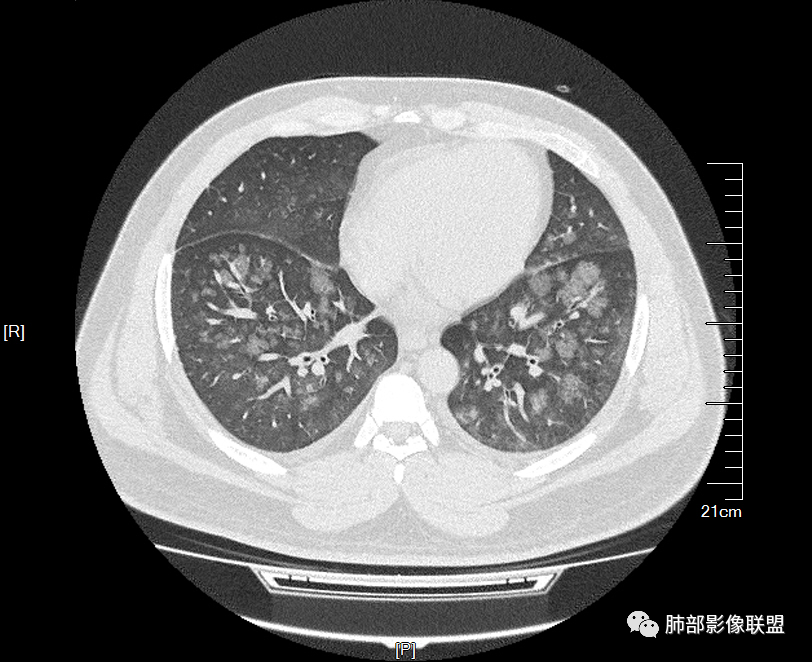

双肺多发弥漫性磨玻璃结节影,大小不一,形态不规则,部分融合,支气管未见明显扩张,部分血管束略增粗,叶裂胸膜增厚,临床有痛风,左足痛6天,考虑:1:痛风结节(一般实性结节,很少磨玻璃结节影)2:血管炎?3:病毒性肺炎(水痘-疱疹肺炎?)

双肺多发腺泡结节及磨玻璃,小叶间隔增厚(大网格状),腺泡结节内及磨玻璃内可见细网格影(小叶内间隔增厚),影像表现符合肺泡出血改变,血肌酐升高,考虑肺肾综合征。鉴别肺水肿。

年轻男性,痛风史,高血压史,肌酐高,左足痛6天入院。胸CT:双肺多发弥漫性磨玻璃结节影,大小不一,部分融合,上中下肺都有,中内带多,胸膜下少。部分血管束略增粗,小叶内间隔、小叶间隔增厚,下肺明显,左室大。叶裂胸膜增厚。临床有痛风,左足痛6天,考虑:心衰、间质性肺水肿?弥漫性肺泡出血?鉴别:MPA,肺肾综合征,痛风结节等。

青年男性,有肾功能不全史和痛风史,这个影像分布有个典型的特点,全部是以中央间质周围的渗出性改变,这个改变主要就是两种可能,一种是肾功能不全导致的血管通透性增高导致的肾性肺水肿,一种是出血导致的DAH改变,具体是哪种,影像上不好简单的鉴别,需要结合更多临床资料综合分析。

多发GGO结节,边界清,以全小叶、小叶中心为主:

小叶间隔增厚,无明显重力趋势

中轴间质增厚,小叶间隔增厚,小叶内间质增厚,部分重力作用,双侧对称,胸水,按理淋巴道回流受阻有

问题是腺泡结节如何解释?

一般吸入性病变,肺泡腔充填性病变

1.间质性肺水肿 :小叶间隔增厚,尚光滑,支气管血管束增粗,胸膜或叶间裂增厚,肺内有磨玻璃密度影,有重力分布趋势。

2.肺泡性肺水肿 :

(1)中央型分布:以肺门为中心,两肺中内带对称分布的大片状实变,称为“蝶翼征”。常见于心源性及肾源性肺水肿患者。也可表现为磨玻璃密度病灶,弥漫性分布或以小叶中心性分布。

(2)弥漫型肺水肿:弥漫分布于两肺内的多发斑片状磨玻璃密度及实变影,大小和密度不等,可融合成大片状阴影,可见空气支气管征。